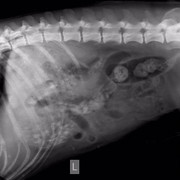

Нас 6-ро, и все они замечательные ребята с большим сердцем. Эта ситуация личная для меня, и я всеми силами хочу сделать добро, вылечить животное, которое я собственноручно вытягивала с проезжей части, которого гладила, пока ему ставили капельницу и измеряли давление врачи круглосуточной ветклиники. Спокойный умный пёс, который оказался на улице по вине человека. Он не щенок, он в самом расцвете, думаю, но такой добрый, отзывчивый и спокойный, и борющийся за жизнь. У собакена перелом таза, сильные ссадины, осколки таза навредили внутренним органам и нужна операция, последующее дорогостоящее и долгое восстановление. Также есть вопросы по дерматологии, пёсель уличный - завтра врачи возьмут соскоб, чтобы попытаться восстановить волосяной покров животного.

Собаке сделали операцию, но не на тазу (таз вправили ректально), а на передней лапе, которая оказалась сломана, но в виду того, что собака была лежачей и болезненно реагировала на перемещения по клинике, про перелом выяснилось позже. Поставили спицы.

У него есть чувствительность задних лап, поэтому проводимость есть. В туалет пошел сам. Врачи говорят операция на тазу не нужна.

Цитата Саша (  )  говорят операция на тазу не нужна.У него перелом таза, что гораздо серьезнее его сломанной и прооперированной лапы. У него же таз перекошен и лучше вряд ли при постоянном движении будет. Снимки таза и пса самого осматривал опытный травматолог?

Ну дело, конечно, хозяйское, или кураторское точнее, но я бы поинтересовалась, какой прогноз лечащий врач даёт при консервативном лечении (вернее нелечении) сломанного таза и когда планируется контроль сращения. Потому что при постоянной подвижности костей в месте перелома таза есть угроза того, что пёс станет инвалидом. При правильном лечении и фиксации - выздоровеет полностью. Здесь ведь на форуме небезразличные люди собрались и советы дают из своего волонтерского опыта (вам советовали везти пса к проверенным опытом травматологам, пч все ветеринары - специалисты широкого профиля, и лишь единицы являются узкими и грамотными специалистами в определённой области, в травматологии в частности, чему учатся годами). Вашему подопечному все желают только скорейшего выздоровления, поэтому и пишут здесь

меня зовут Алена и я одна из очевидцев и посетителей Собакена. спасибо большое, за ваше внимание к нашей истории и за желание помочь!!на данный момент его снимки смотрели в САСе, а также лечащий врач моего кота (Мурыченков Евгений - отличный врач, много раз возвращал моего Зефира с того света). оба врача сейчас подтвердили что таз оперировать нет необходимости, как нам объяснили процесс заживления будет в обоих случаях аналогичный (шуруп Собакен может вырвать случайно, при постановке шурупа этого возможно повредить нервы). чувствительность ног у него в порядке. соскоб на клеща делали, но его не нашли, возможно это нарушение функции надпочечников. но нам порекомендовали полечиться от клеща после того как у него восстановится печень (сейчас множественные ушибы внутренних органов)